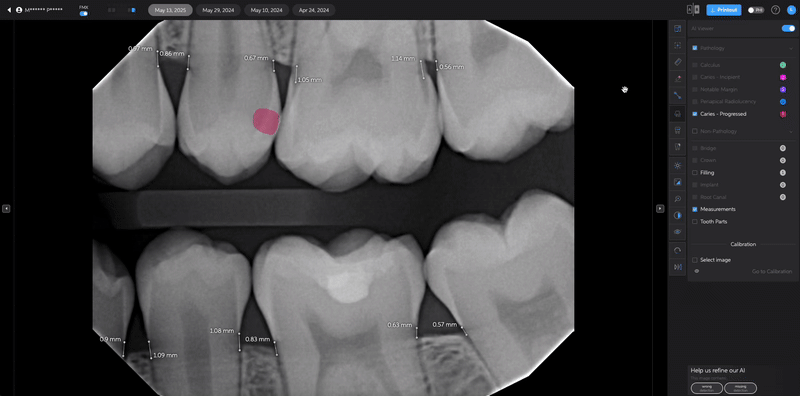

- Manually Add a Detection

- Select the Edit Tool.

- Choose your preferred shape:

- Draw a square

- Draw a polygon

Polygons allow more precise marking for certain conditions like caries and periapical radiolucencies.